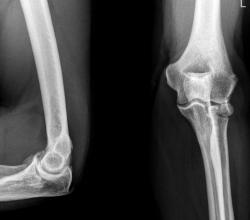

Хотелось-бы услышать мнение коллег и коллеги Вега, по поводу, помеченного красными стрелками, и откуда "это" оторвалось и что это за штука. Мне до конца субстрат данного тенеобразования не понятен.

Да, прекрасно виден субкапитальный перелом лучевой кости, с распространением линии перелома на суставную поверхность головки. Но что с локтевым отростком локтевой кости. Что с контуром локтевого отростка, помеченного зелеными стрелками, он довольно плохо дифференцируется, на мой взгляд там и "ступенька" намечается? Или "игра теней"?

А что это за дополнительная тень на фоне локтевого отростка? На мой вгляд, чтобы с ней разобраться, надо произвести рентгенографию локтевого сустава в "косых проекциях".

На мой взгляд, боковая проекция, еще более "интересная", чем "прямая". Понятно, что "изменения" - желтые стрелки имеют отношение к лучевой кости, а вот к "чему" имеют отношение "изменения" в теневой картине, помеченные "красными" стрелками?

НУ ОЧЕНЬ ИНТЕРЕСНЫЙ ПЕРЕЛОМ. И дополнительные снимки , произведенные в косых проекциях, могли-бы пролить определенный свет, на возникающие вопросы.

Уважаемые коллеги! Перелом, без сомнения, довольно редкий. На мой взгляд имеется внутрисуставной перелом головки лучевой кости с ротацией отломка суставной поверхностью кнаружи на 90 градусов. В таких случаях меня всегда, в первую очередь, интересует механизм травмы, приложение повреждающей силы. С локтевым отростком думаю все в порядке.

Что касается фрагмента суставной поверхности головки луча, отмеченного красными стрелками - как откроем сустав, так и будет видно: если встанет на место и нормально удержится - оставим, если нет - удалим. И зафиксируем основной отломок шурупом.